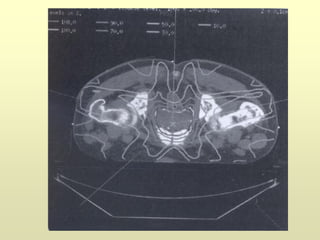

Estadificación

T2: tumor localizado dentro de la próstata

T3a: Tumor que afecta la cápsula

T3b: Invasión de vesículas seminales

T4: invasión de órganos adyacentes (recto, vejiga…)

Estadificación T2: tumor localizadodentro de la próstata T3a: Tumor que afecta la cápsula T3b: Invasión de vesículas seminales T4: invasión de órganos adyacentes (recto, vejiga…)